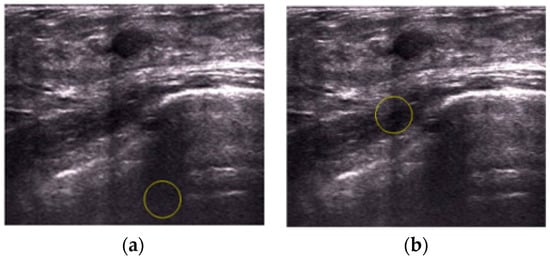

An Automatic Localization Algorithm for Ultrasound Breast Tumors Based on Human Visual Mechanism